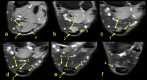

The aim of the study was to check if the subtendons of the Achilles tendon can be identified in vivo on MRI in the midportion of the tendon. The relation of the plantaris tendon to the Achilles tendon was also examined. A retrospective study of 200 MRI of ankle joints including the Achilles tendon was conducted. Statistical analysis of the correlation between the possibility of identifying the subtendons and the side, gender, presence of the central soleus tendon and plantaris tendon variation was performed. The inter-observer agreement between two reviewers in their evaluation of the subtendons was assessed using kappa statistics. The subtendon from the lateral head of the gastrocnemius muscle was identified in 65% (k = 0.63) and was located in the anterior part of the Achilles tendon. The subtendon from the soleus muscle was recognized in 12% (k = 0.75) comprising anterior part of the tendon. In 6% the subtendon from the medial head of the gastrocnemius muscle was identified (k = 0.58). The central soleus tendon was identified in 85% of cases. Statistical analysis shows the weak correlation of the presence of the central soleus tendon and the possibility of identifying the subtendon from the soleus muscle. The plantaris tendon was directly related to the insertion of the Achilles tendon in 42.5%. Identification of the subtendons of the Achilles tendon on MRI is challenging, and most often it is only possible to find the subtendon of the lateral head of the gastrocnemius muscle.